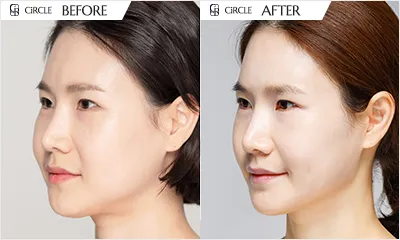

Scars

Pores